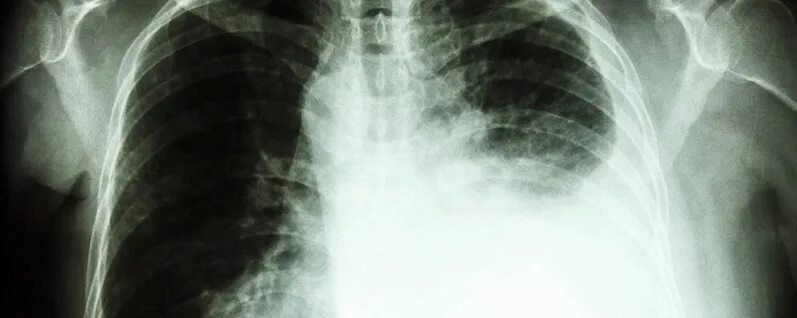

Рак легких 1